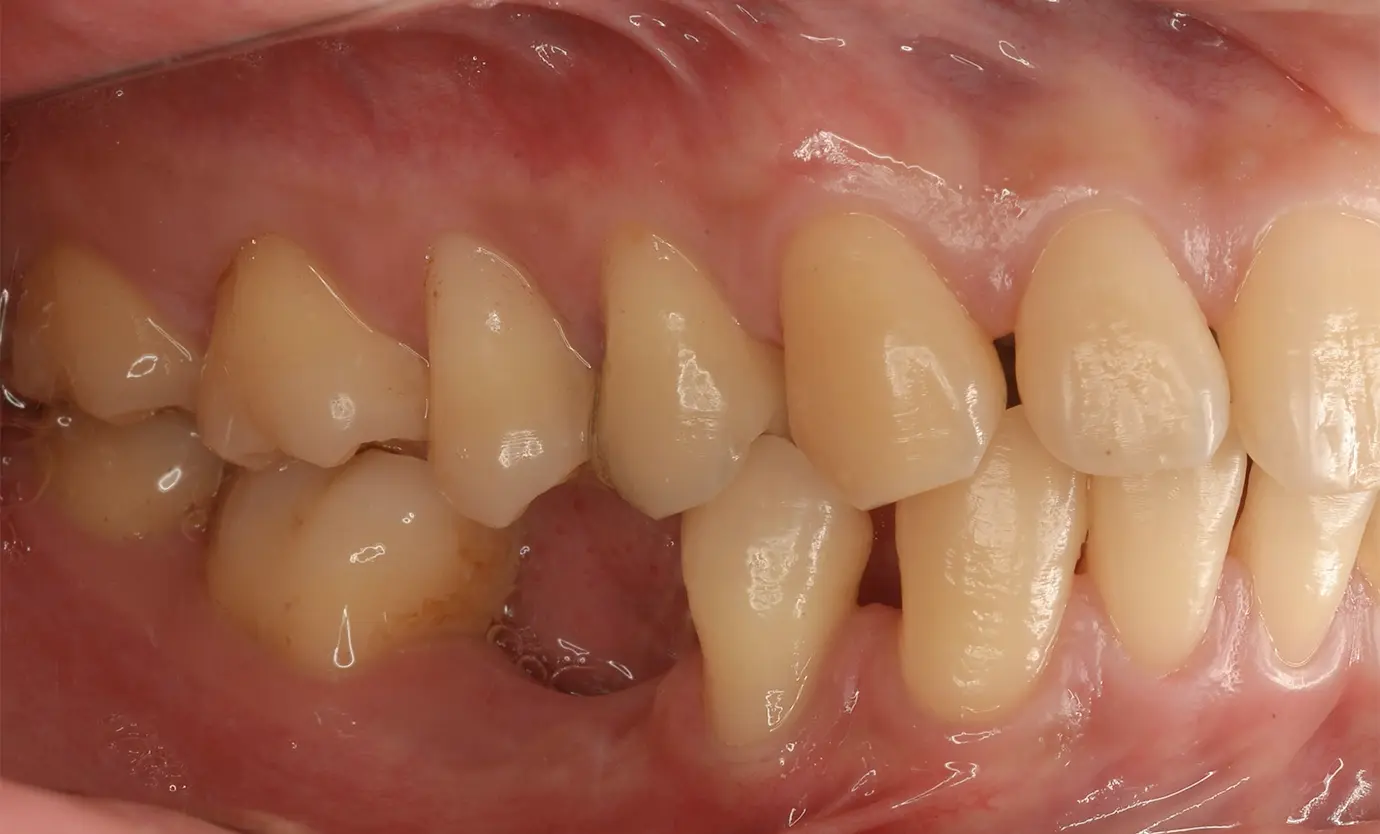

インプラント治療は、何らかの理由で歯を失った方が、天然歯に近い見た目と、

しっかり噛める感覚を回復することを目的とした治療です。噛む機能だけでなく、

見た目の美しさにも配慮しながら進めます。

ただし、顎の骨の状態やお口の症状によっては、治療の適用が難しい場合もあります。

インプラントは、失った歯の部分だけを補う治療です。ブリッジのように、両隣の健康な歯を削って支えにする必要はありません。そのため、周囲の歯への負担を抑えながら治療を進めることができます。

インプラントは、顎の骨に固定する治療のため、天然の歯のような噛み心地をめざせる上、噛む力が顎の骨に伝わりやすい特徴があります。その刺激によって、顎の骨がやせていく変化を抑えることも期待できます。

さまざまな事情で、すぐに治療を始められない場合があるかもしれませんが、歯がない状態が続くと、かみ合わせのバランスが変わり、噛みにくさを感じたり見た目が気になったりすることがあります。